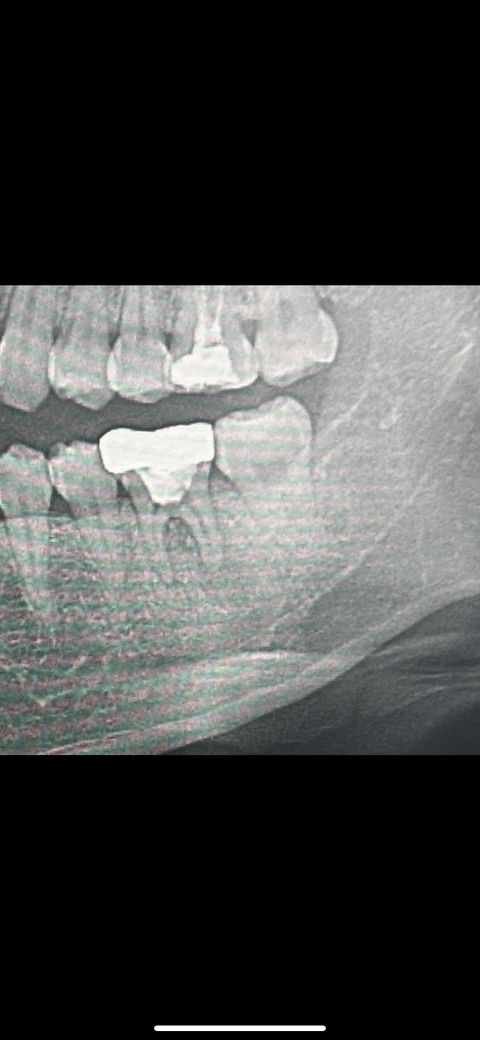

어금니 염증으로 통증이 있습니다 꼭 발치해야 할까요?

통증이 있고 염증이 심한상태라고 발치 후 임플란트 권장하였습니다 최대한 자연치아를 꼭 살리고 싶은데 도저히 가망히 없는지 궁금합니다

염증이 너무 많이 진행된 경우에는 치아를 살리기 힘든 경우가 많으며 위의 치아도 살리기 어려워 보입니다.

• 사진으로 봤을 경우에는 씨앗 뿌리에 뒤쪽으로 해서 깊은 병소가 보입니다 시야가 파절되었을 때 해당 사진과 같은 증상이 나타나는 경우가 많이 있습니다.

치아가 파절되어서 생긴 증상이라면 치아를 발치해 줘야 할 수도 있습니다 자세한 확인을 위해서 치과에서 진료를 받아 보세요.

• 염증이 아주 심한 상태는 맞습니다 염증이 잇몸뼈까지 많이 퍼져서 잇몸뼈를 녹인 상태이고요 이 상태에서 신경치료 및 잇몸치료를 진행한다 쳐도 치아자체를 오래 유지하지 못할수도 있습니다

신경치료하고 잇몸치료하는 것도 험난한 과정이고 여러번 내원하고 하느라 불편할 수 있는데 그렇게 해도 치아를 살리지 못하게 될 가능성이 높으므로 그럴꺼면 그냥 빼고 임플란트를 하자고 하신 겁니다.